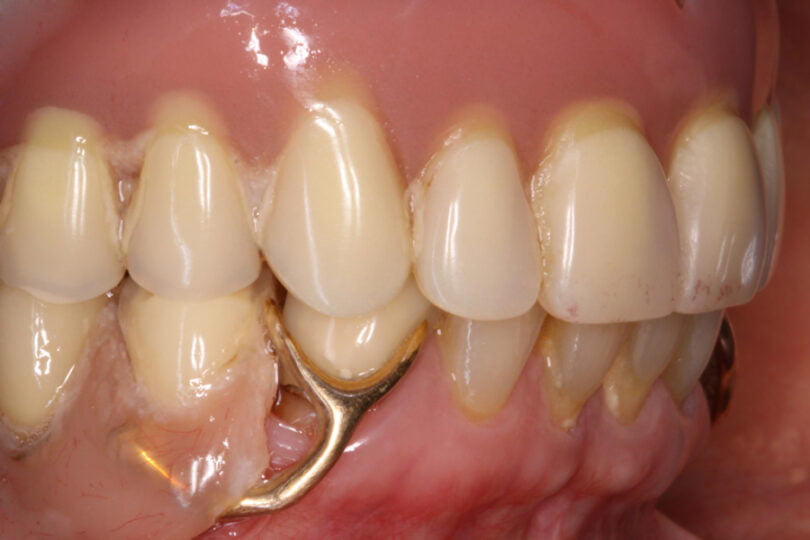

Quatro dos seis implantes foram de 5,5 mm de comprimento por 5 mm de diâmetro, um implante foi de 6,5 mm de comprimento por 3,75 mm de diâmetro e o último implante foi de 6,5 mm de comprimento por 5 mm de diâmetro (figura 2).

As seguintes imagens apresentam um dos casos incluídos no estudo (figura 03 – 15).